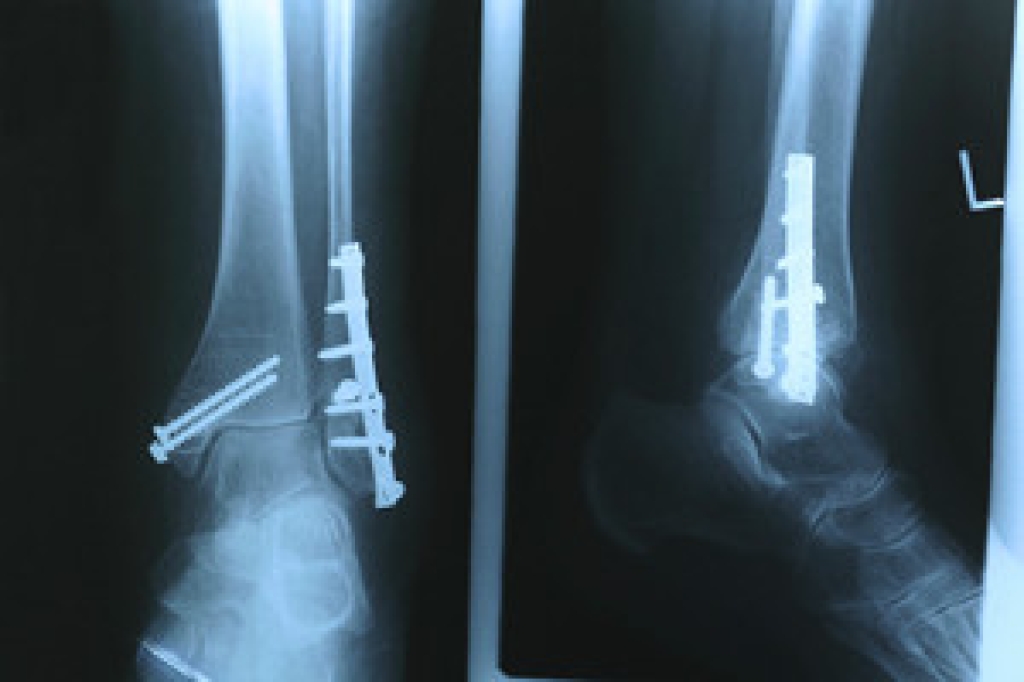

Foot and ankle trauma is a prevalent issue, especially ankle injuries, which can significantly affect mobility. Among the common types of ankle fractures are isolated fibular fractures and Danis-Weber fractures, classified into types A, B, and C. An isolated fibular fracture involves the fibula and is typically less severe. Danis-Weber type A fractures occur below the ligament complex, a group of ligaments that connect the tibia, or shinbone, and the fibula, the smaller bone next to the tibia, just above the ankle joint. A type B fracture is at the level of the ligament complex, and a type C fracture is above the ligament complex, often accompanied by an injury in this area. Treatment for these fractures ranges from immobilization with a cast or brace for less severe cases to surgical intervention for more complex fractures. Potential complications can include chronic pain, instability, and post-traumatic arthritis, which can impede recovery and long-term function. Given the complexities and potential for complications, if you have an ankle fracture, it is suggested that you schedule an appointment with a podiatrist for an accurate diagnosis, effective treatment, and optimal recovery.

A broken ankle is experienced when a person fractures their tibia or fibula in the lower leg and ankle area. Both of these bones are attached at the bottom of the leg and combine to form what we know to be our ankle.

When a physician is referring to a break of the ankle, he or she is usually referring to a break in the area where the tibia and fibula are joined to create our ankle joint. Ankles are more prone to fractures because the ankle is an area that suffers a lot of pressure and stress. There are some obvious signs when a person experiences a fractured ankle, and the following symptoms may be present.